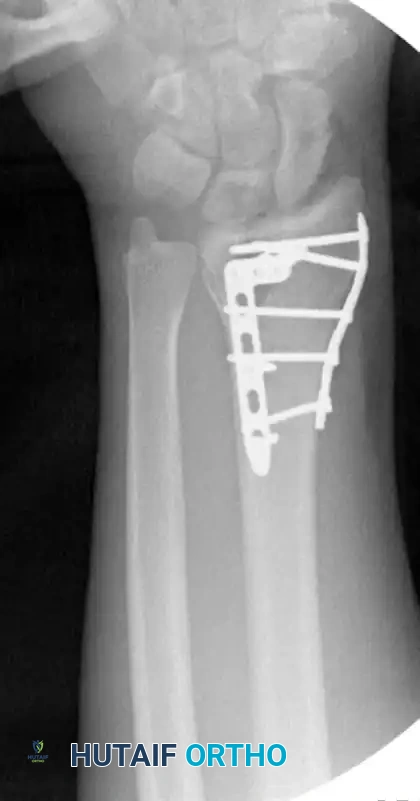

Image

Postoperative AP radiograph demonstrating anatomic restoration of radial height and inclination utilizing fragment-specific fixation.